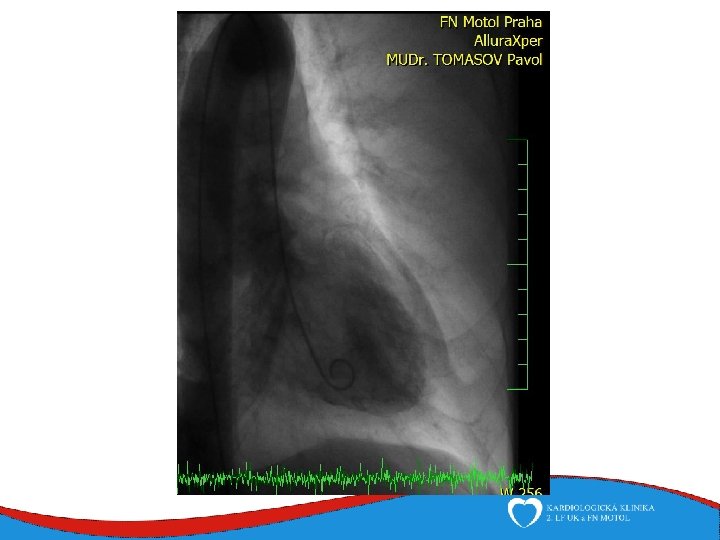

Case report Woman, 75 years Comes to ED for new-onset chest pain and weakness History: hyperthyreosis Drugs: Thyrozol Family history: no cardiovascular diseases Physical: BP 105/70, HR 92/min, RR 20 breaths/min, sat O 2 94%

ECHO – anterior wall akinesis, LV EF 35%, mild mitral regurgitation, no dilation of right-sided chambers, no pericardial effusion

1

Tako-tsubo